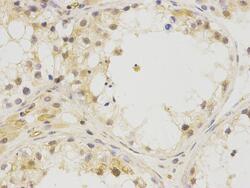

Immunohistochemistry

PA5-85984 IHC

Full details

Method: